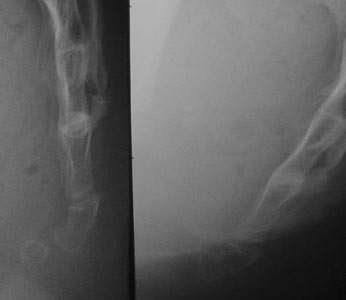

Case #5: The need for excellent radiographs. Left : standard film. Center : dynamic film, which appears normal... but the distal vertebra is not seen. It is annoying, because it was the one which was luxated (right, X)